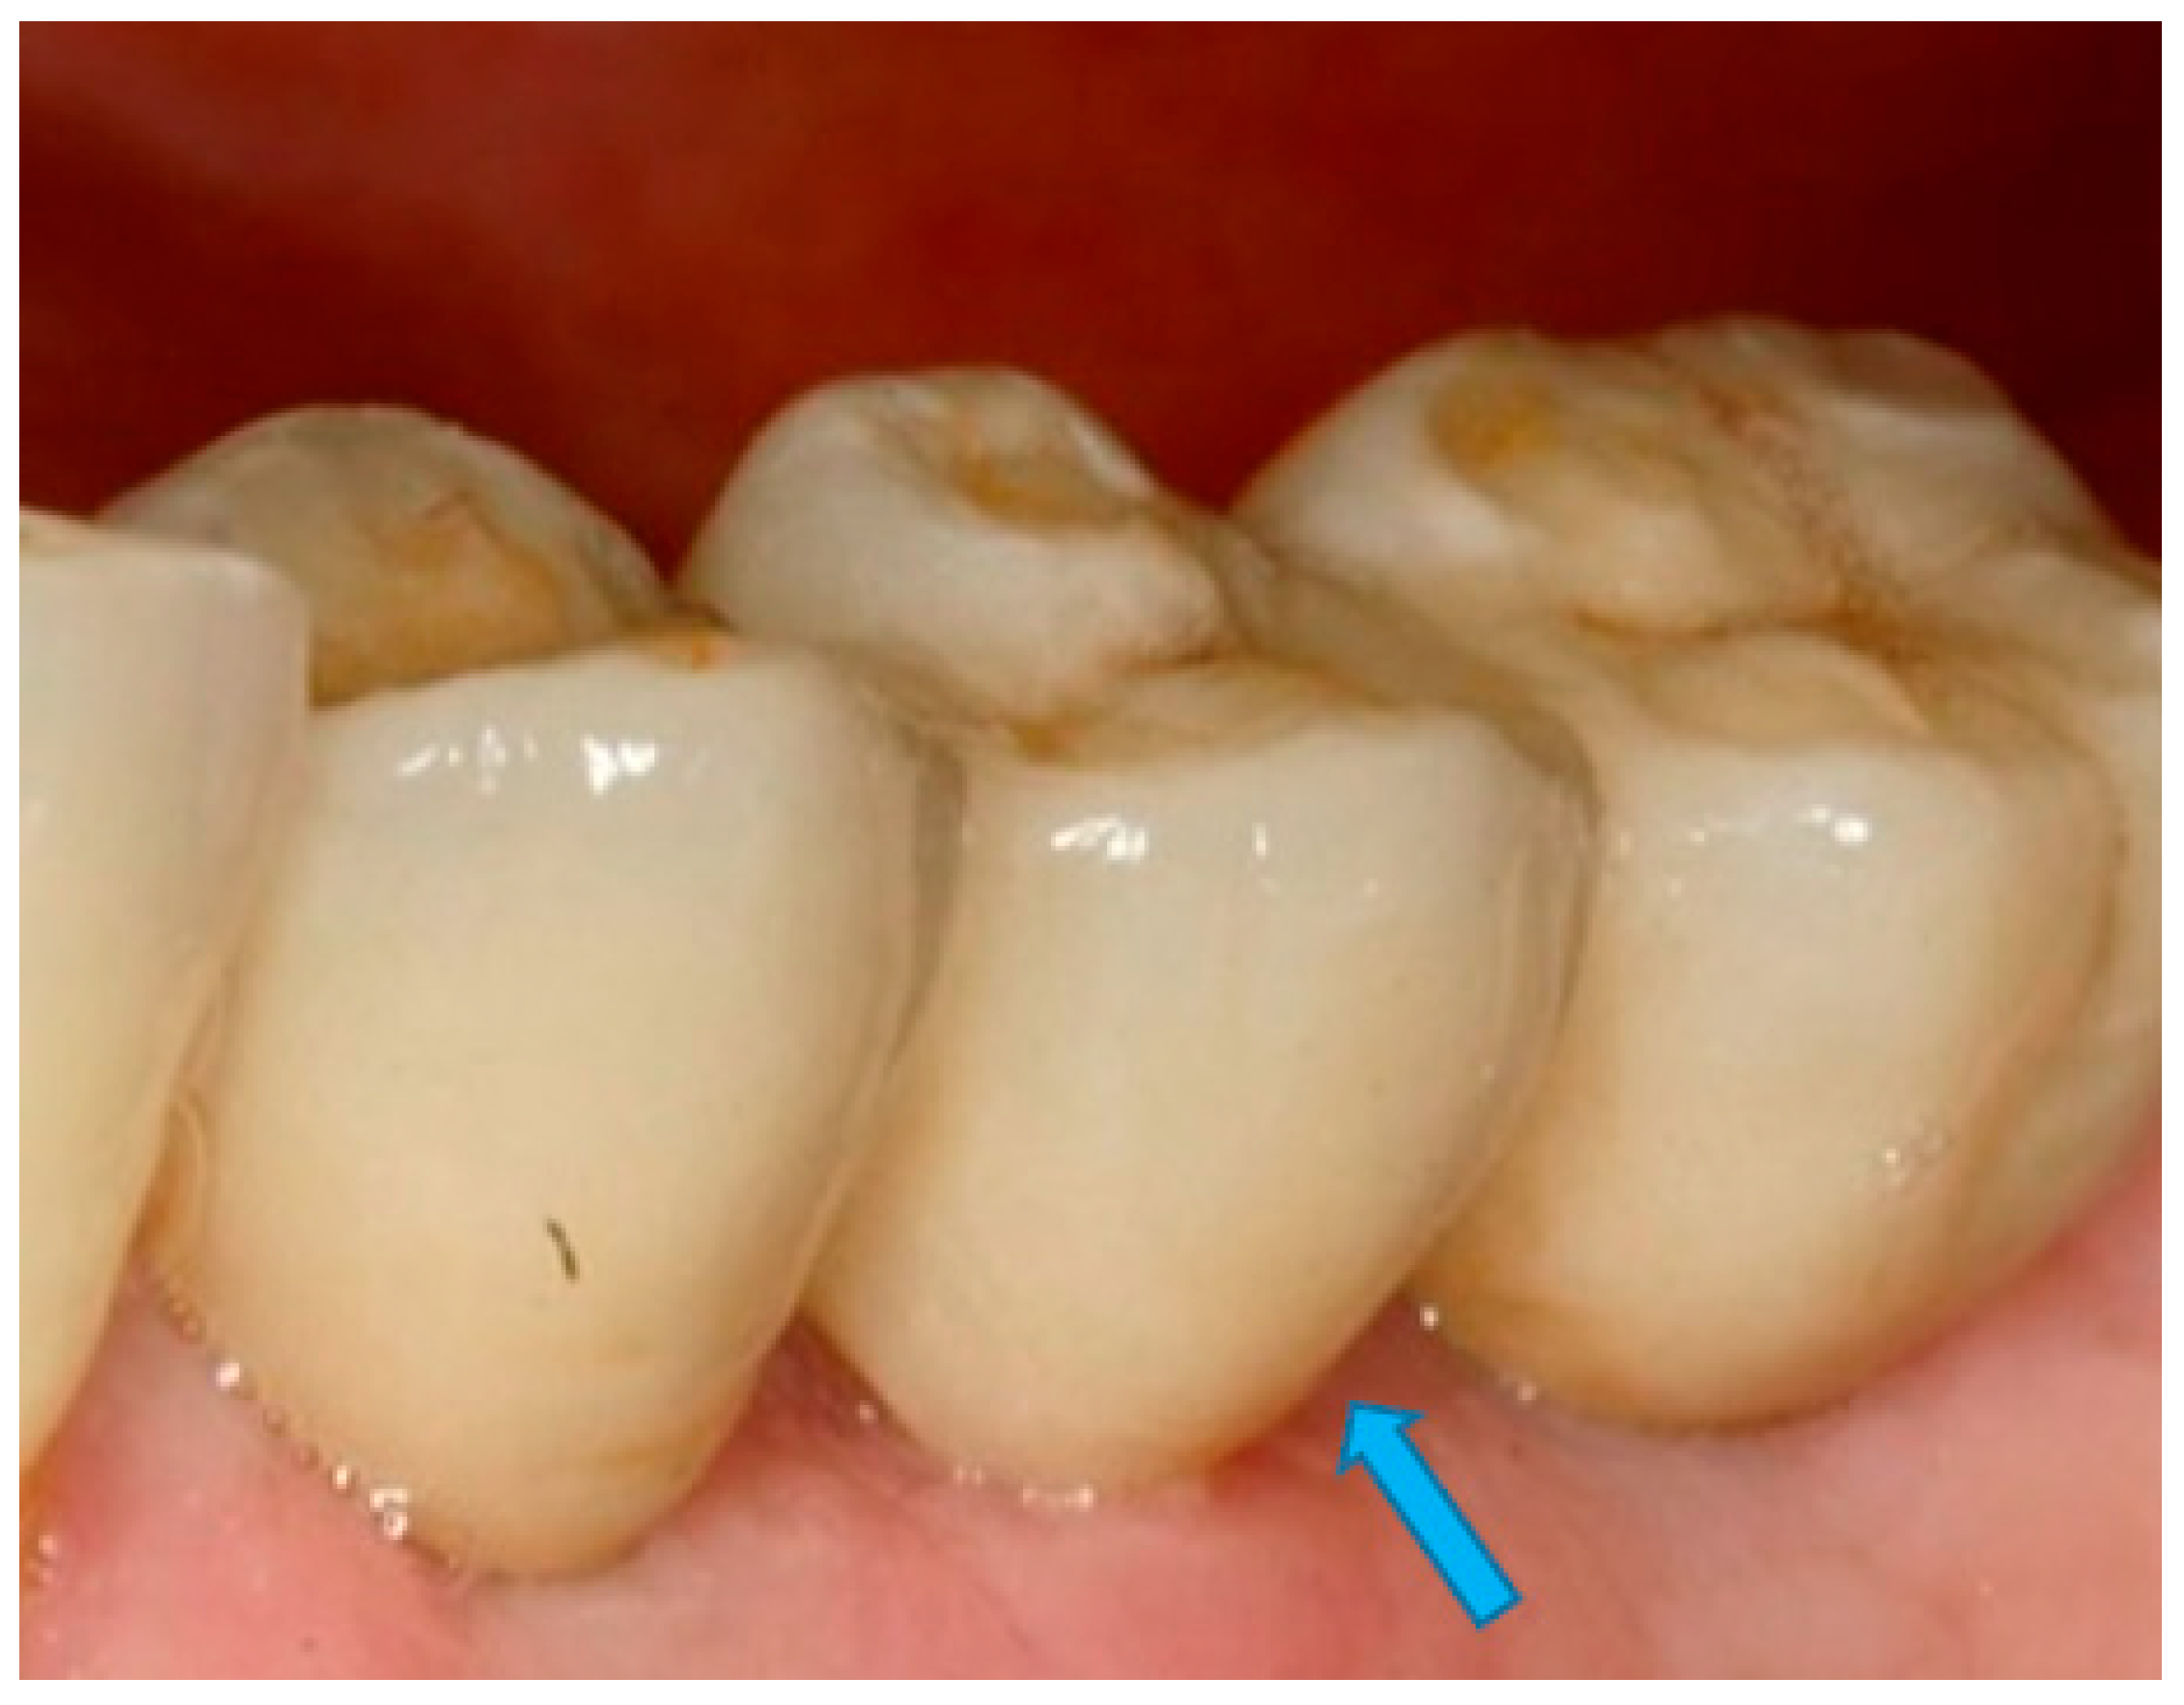

- Measurement of mesial and distal bone loss: Clinically, an increase in the probing depth of the peri-implant pockets, both mesial and distal, was recorded using a calibrated probe with a force of 0.25 N. Radiographically, mesial and distal peri-implant bone height loss was measured using properly performed radiological projections. In fewer than five patients, statistically significant findings in cases of bone loss were difficult to achieve.